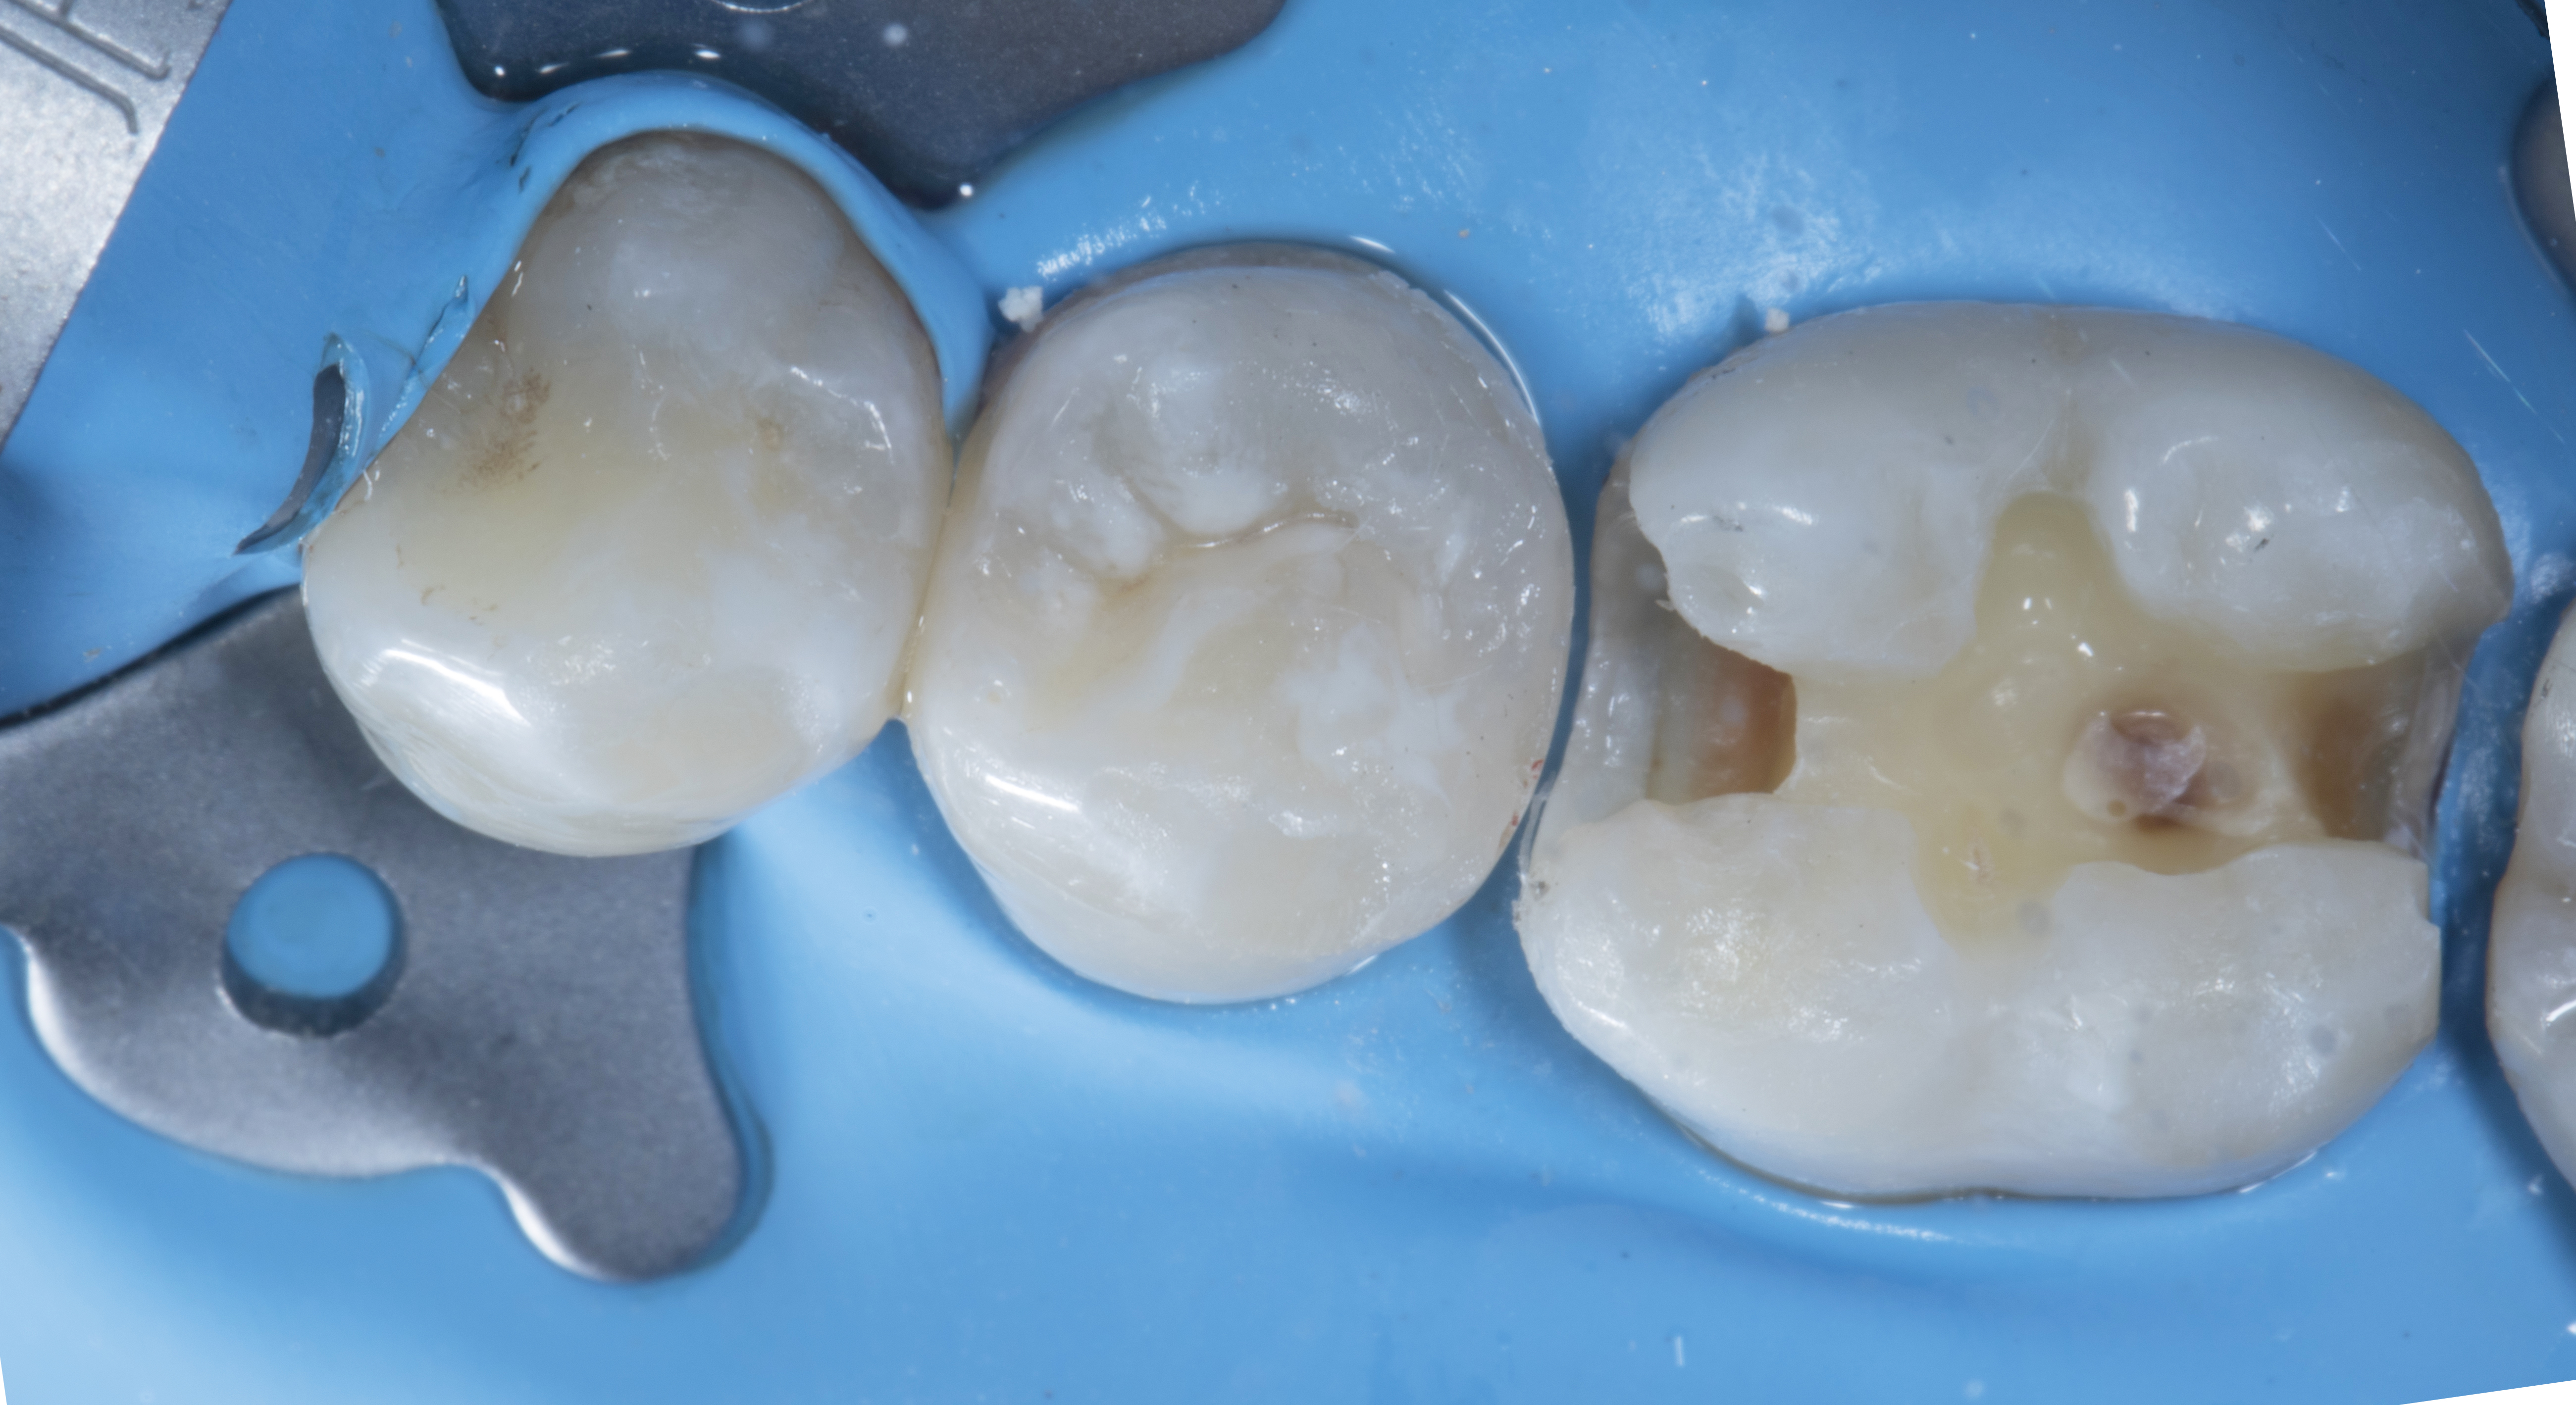

A 25 Years old male patient visited the clinic with a carious lesion on tooth #35 distally and #36 both mesially and distally. Tooth # 36 shows old composite restoration. The patient complains of sensitivity in the 35-36 region when exposed to cold or sweet.

Figure 1

Figure 1. A carious lesion on tooth #35 distally and #36 both mesially and distally. Tooth #36 shows old composite restoration.